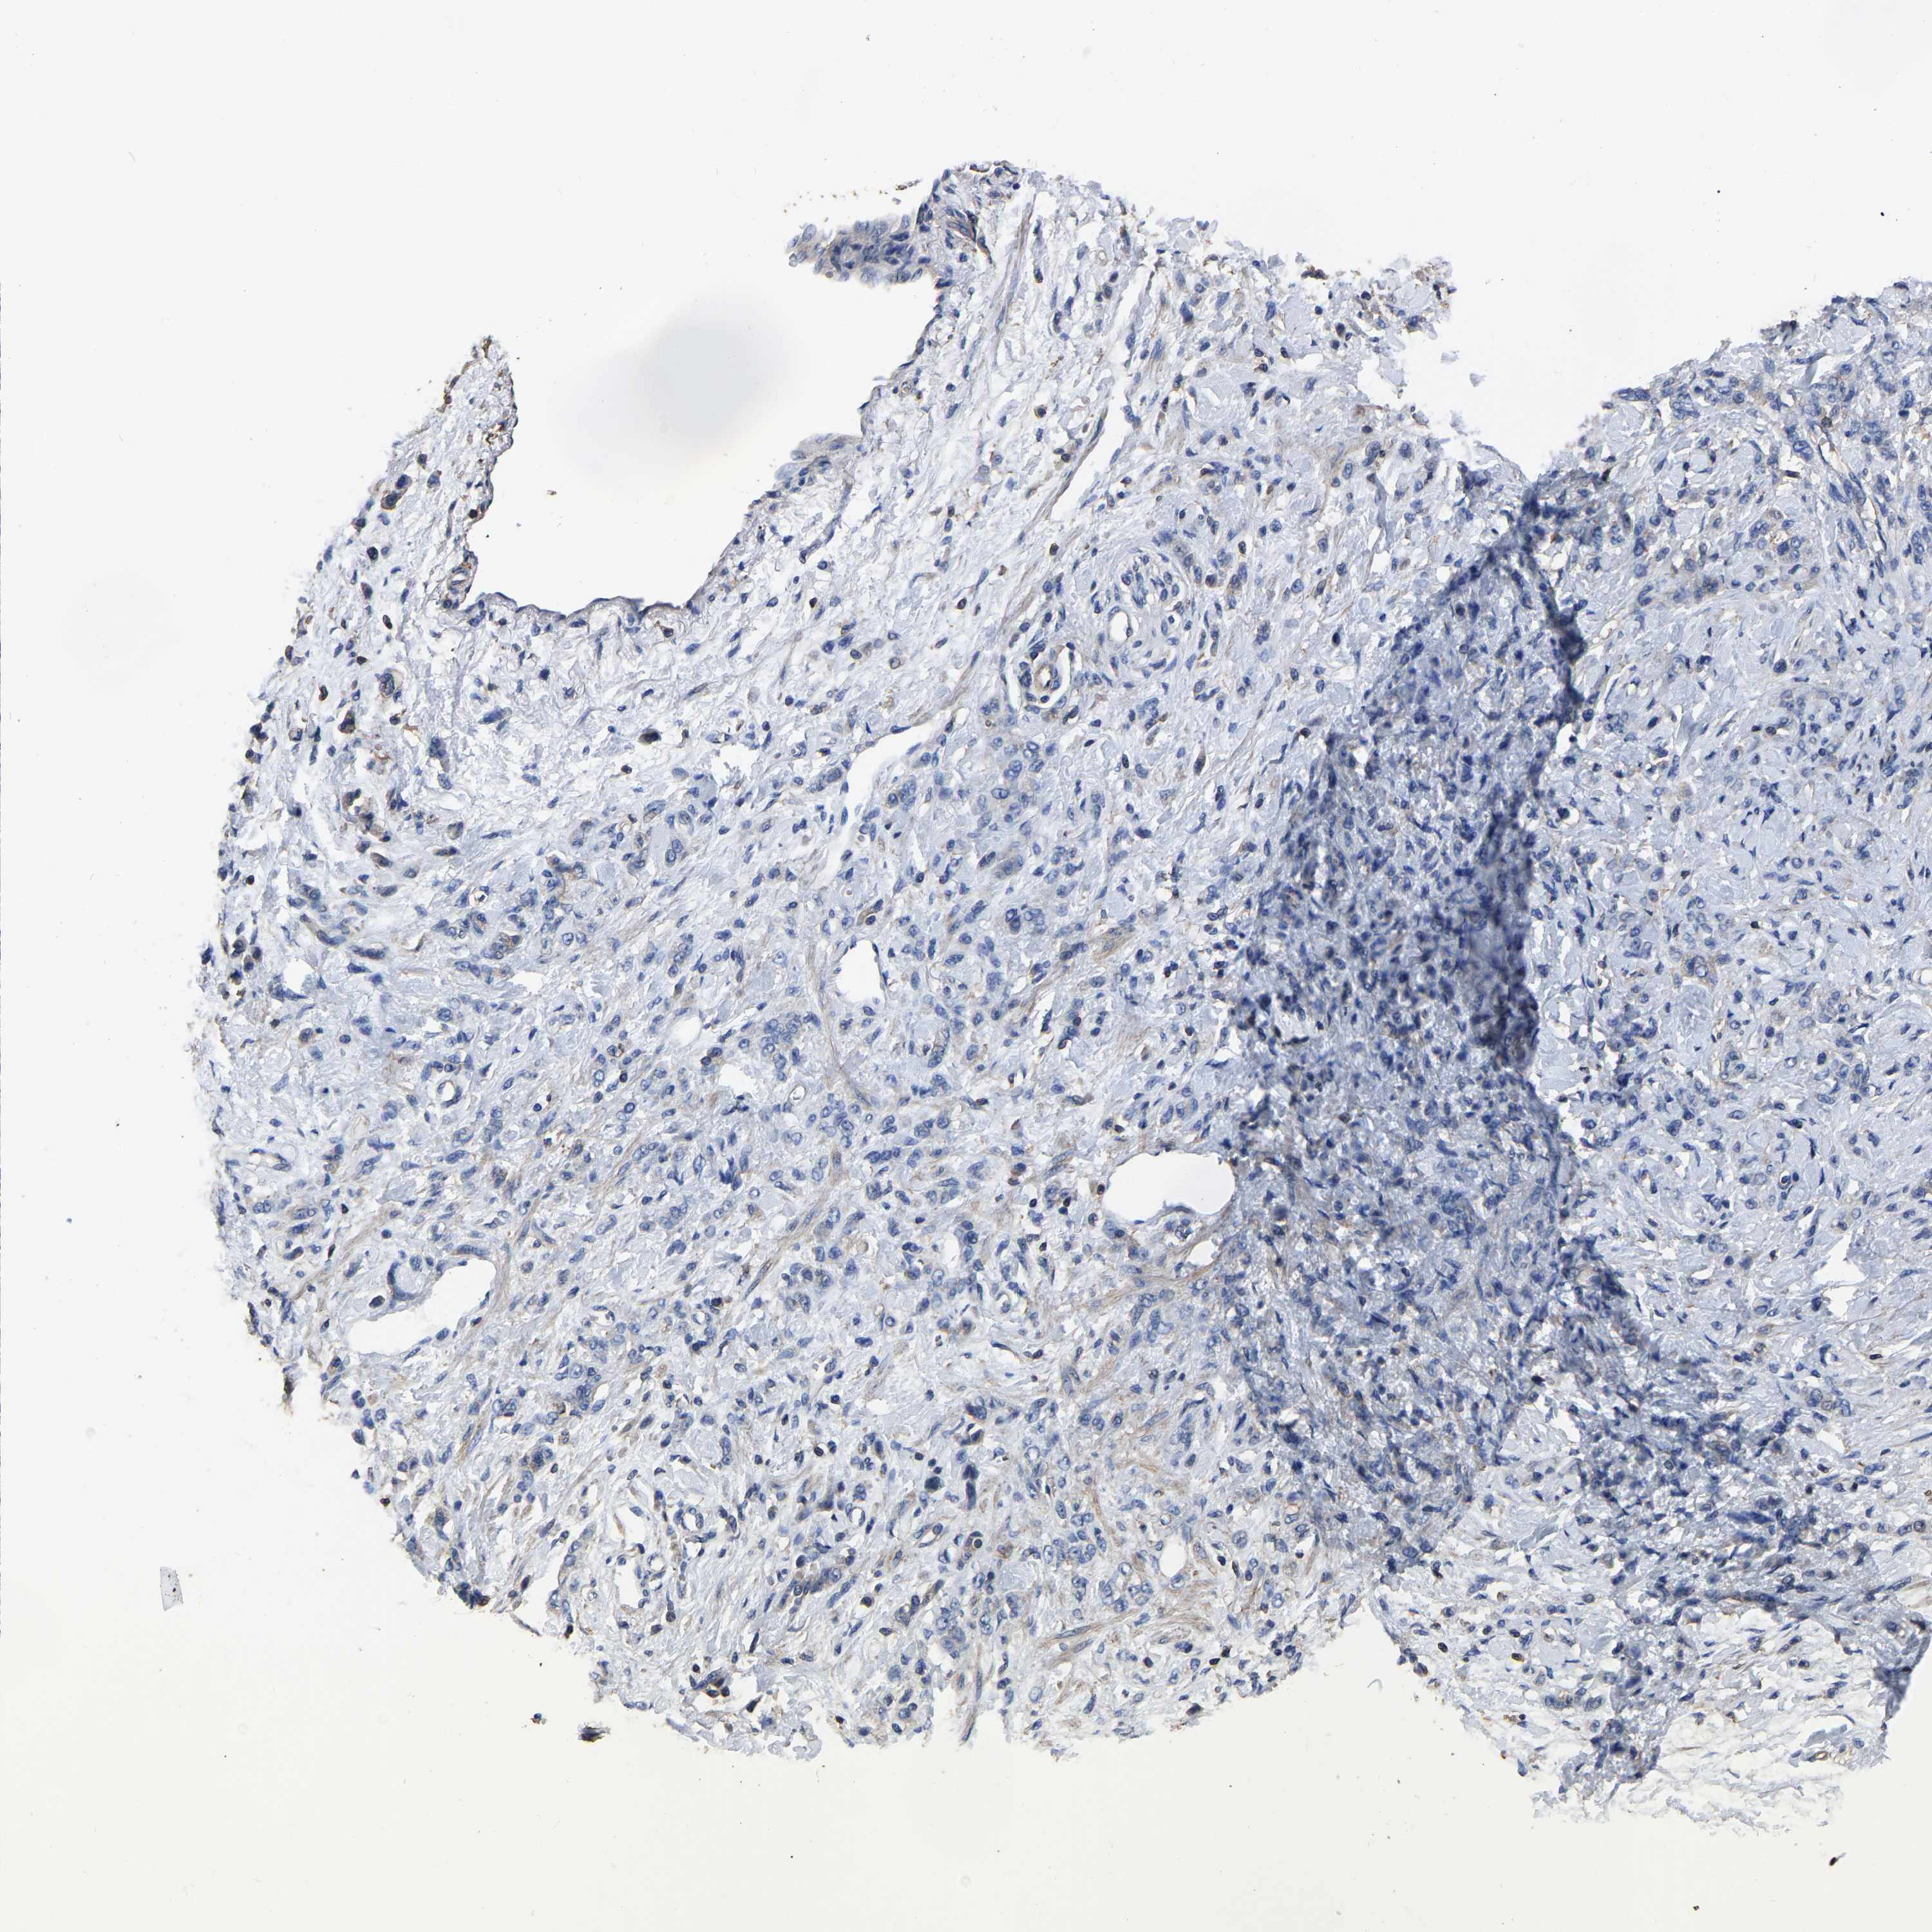

STOMACH CANCER - Protein expressioni

A mouse-over function shows sample information and annotation data. Click on an image to view it in a full screen mode. Samples can be filtered based on level of antibody staining by selecting one or several of the following categories: high, medium, low and not detected. The assay and annotation is described here.

Note that samples used for immunohistochemistry by the Human Protein Atlas do not correspond to samples in the TCGA dataset.

Antibody stainingi

Antibody staining in the annotated cell types in the current human tissue is reported as not detected, low, medium, or high, based on conventional immunohistochemistry profiling in selected tissues. This score is based on the combination of the staining intensity and fraction of stained cells.

Each image is clickable and will lead to virtual microscopy that enables deeper exploration of all samples and also displays staining intensity scores, fraction scores and subcellular localization as well as patient and tissue information for each sample.

Antibody HPA003004

Antibody HPA005819

Staining

High

Medium

Low

Not detected

Intensity

Strong

Moderate

Weak

Negative

Quantity

>75%

75%-25%

<25%

None

Location

Nuclear

Cytoplasmic/membranous

Cytoplasmic/membranous,nuclear

Adenocarcinoma, NOS